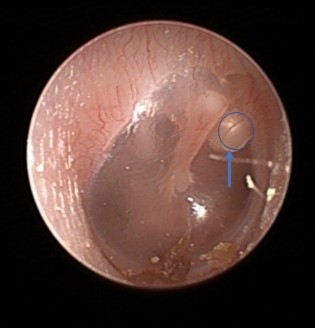

| ▲진주종 1기 내시경 사진 [한림대동탄성심병원 제공] |

선천성 진주종은 고막이 생성되는 과정에서 고막 외부에 위치해야 하는 상피조직이 고막 안쪽에 남아서 계속 자라게 되며 발생한다. 진주종이 계속 커지게 되면, 청력이 떨어지고 귀속 뼈를 손상시켜 어지럼증이 생길 수 있으며, 심하면 안면신경마비까지 일으킬 수 있다.

선천성 진주종을 앓는 소아의 대부분이 감기나 중이염으로 병원을 찾았을 때 귓속을 검사하면서 진주종을 발견해 치료를 받게 된다. 진주종은 수술을 통해 제거하게 되는데 이때 진주종의 크기와 진행정도(1~4단계)에 따라 수술범위가 결정된다.